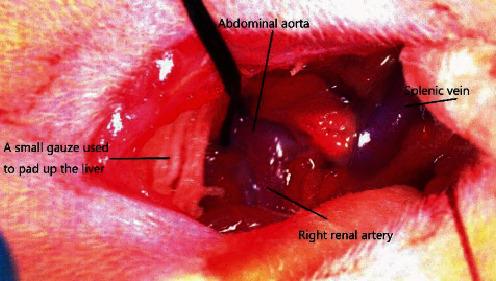

Heart failure is a complex clinical syndrome in which ventricular filling or ejection capacity is impaired due to structural or functional diseases of the heart. In order to establish a stable heart failure model, we investigated cardiac parameters in rats with abdominal aortic contraction and normal rats, including the left ventricular posterior wall diameter (LVPWd), the interventricular septum thickness of end-diastolic (IVSd), the left ventricular end-diastolic diameter (LVEDd), the left ventricular ejection fraction (LVEF), and left ventricular fractional shortening (LVFS). Rats were randomly divided into experimental group ( = 20) and control group ( = 20). The experimental group underwent modified abdominal aortic constriction, while the control group only isolated the abdominal aorta without constriction. The results showed that the survival rate of rats in the experimental group was 85% after one week of operation, while the survival rate of rats in the control group was 100%. Five weeks after operation, the left ventricular posterior wall diameter (LVPWd) and the interventricular septum thickness of end-diastolic (IVSd) in the experimental group were all increased compared with those in the control group, and the differences were statistically significant ( < 0.05); the left ventricular end-diastolic diameter (LVEDd) in the experimental group showed an increasing trend compared with the control group, but > 0.05; compared with the control group, the left ventricular ejection fraction (LVEF) and left ventricular fractional shortening (LVFS) in the experimental group showed downward trend, but > 0.05. 10 weeks after operation, the LVPWd, IVSd, and LVEDd of the experimental group were increased compared with the control group, < 0.05, and the LVEF and LVFS of the experimental group were decreased compared with the control group, < 0.05. Compared with the control group, the BNP of the experimental group increased significantly, < 0.05. The heart weight index and left ventricular weight index of rats in the experimental group were significantly higher than those in the control group, < 0.05. HE staining showed that the myocardial cells in the experimental group increased in volume, disordered cell arrangement, widened gaps, increased nuclear hyperchromia, and uneven staining. This paper provides a theoretical basis for the study of heart failure.

心力衰竭是一种复杂的临床综合征,由于心脏的结构或功能疾病,心室充盈或射血能力受损。为了建立稳定的心力衰竭模型,我们研究了腹主动脉缩窄大鼠和正常大鼠的心脏参数,包括左心室后壁直径(LVPWd)、舒张末期室间隔厚度(IVSd)、左心室舒张末期直径(LVEDd)、左心室射血分数(LVEF)和左心室短轴缩短率(LVFS)。大鼠随机分为实验组(n=20)和对照组(n=20)。实验组行改良腹主动脉缩窄,对照组仅分离腹主动脉而不缩窄。结果显示,术后一周实验组大鼠存活率为 85%,对照组大鼠存活率为 100%。术后 5 周,实验组大鼠左心室后壁直径(LVPWd)和舒张末期室间隔厚度(IVSd)均较对照组升高,差异有统计学意义(<0.05);实验组大鼠左心室舒张末期直径(LVEDd)较对照组呈增高趋势,但>0.05;与对照组相比,实验组大鼠左心室射血分数(LVEF)和左心室短轴缩短率(LVFS)呈下降趋势,但>0.05。术后 10 周,实验组大鼠 LVPWd、IVSd 和 LVEDd 较对照组升高,<0.05,LVEF 和 LVFS 较对照组降低,<0.05。与对照组相比,实验组大鼠 BNP 明显升高,<0.05。实验组大鼠心脏重量指数和左心室重量指数明显高于对照组,<0.05。HE 染色显示实验组大鼠心肌细胞体积增大,细胞排列紊乱,间隙增宽,核深染,染色不均。本文为心力衰竭的研究提供了理论依据。